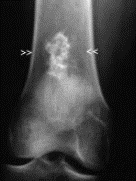

overabundance of organic matrix that is not mineralized, due to a deficiency of vitamin D; see widening of osteoid seams

How well did you know this?